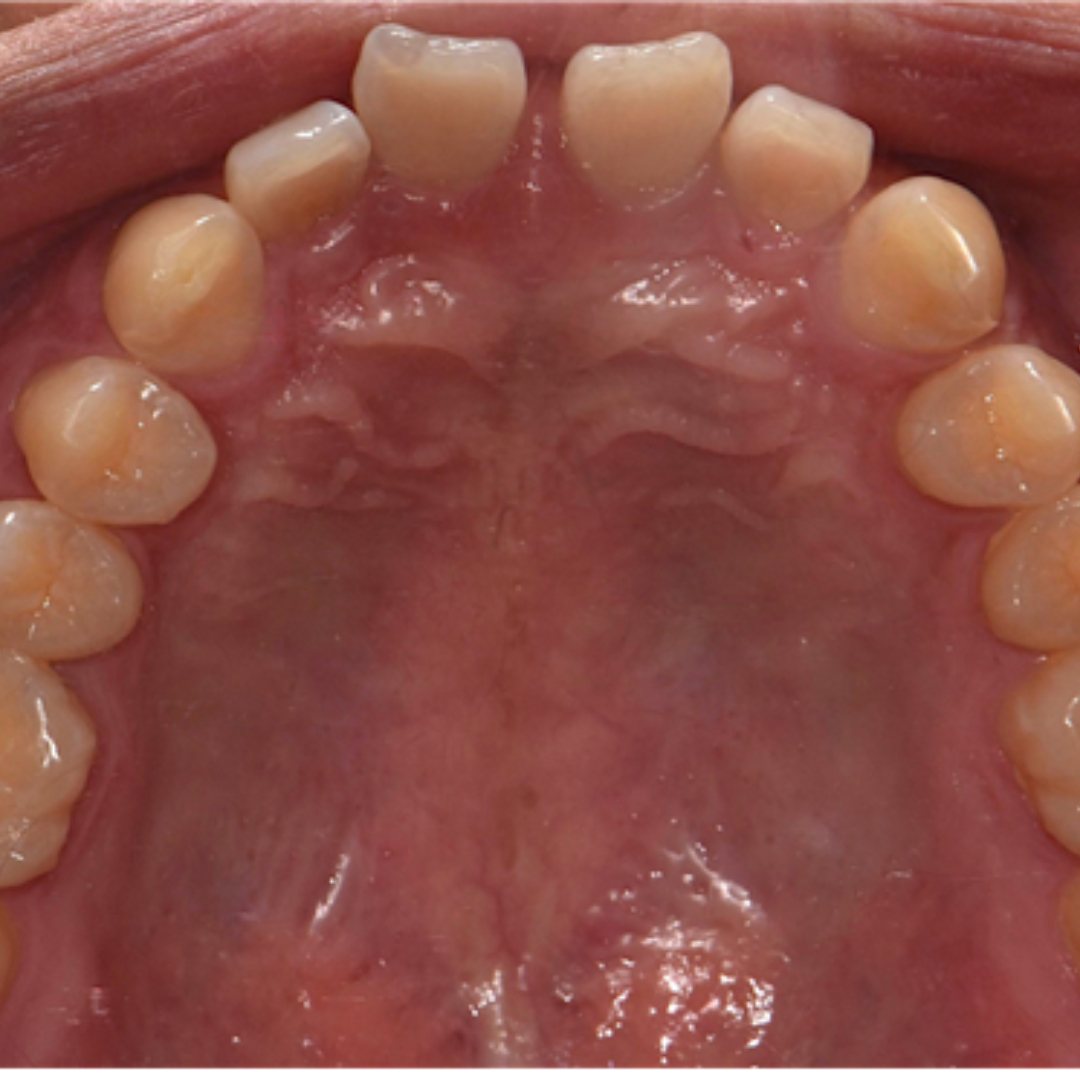

앞니 사이 벌어진 공간과 정중선 불일치를 고민으로 내원하셨던 20대 남성 환자분입니다. 윗니, 아랫니 공간이 각각 3.4mm, 2.6mm 가량 벌어져있고, 위와 아래의 중앙선 차이가 2.1mm 정도로, 상대적으로 정중이개와 정중선 불일치가 눈에 띄는 모습입니다. 해당 환자분께서는 격투기를 취미로 하시는 분이셔서 교정장치를 부착한 채로 얼굴 부위에 타격이 있을 경우 입 안이 다칠까봐 걱정이 있으셨습니다. 교정 진단 상담 후 고민 끝에 부상 방지를 위해 표면이 매끈한 투명교정 장치로 치료하시기로 결정하셨습니다.

최근에는 티 나지 않는 교정을 원하시는 심미적인 이유 뿐만 아니라, 위생 관리, 음식물 섭취, 부상 방지 등 다양한 이유로 전통적인 부착식 교정장치 대신 투명 교정을 선택하시는 환자분들이 부쩍 많아지셨습니다. 투명 교정 치료는 결과는 동일하면서 사진 촬영, 운동, 여행 등 일상 생활에 제약이 크게 없다는 점이 큰 장점입니다. 다만, 증례에 따라 부착식 교정장치가 더 빠르고 효과적인 경우도 있어 교정 치료 전 전문의와의 상담을 통해 결정하는 것이 좋습니다. ^^ 총 32주 간의 교정 치료가 종료된 모습입니다. 기존에 가장 고민이셨던 공간 벌어짐, 정중선 불일치가 예쁘게 수정되었습니다. 2025.5.18.

치료 전, 후 미소가 눈에 띄게 개선되었습니다. 정면에서 두드러지게 보였던 정중 이개와 정중선 불일치가, 벌어진 공간이 폐쇄되고 가지런하게 배열되니 깔끔하고 정돈된 인상을 줍니다. 앞니의 벌어진 공간 폐쇄를 위해 라미네이트나 크라운 치료로 심미적이고 즉각적인 개선을 가져오는 경우도 있습니다. 하지만 위 환자분의 경우 다른 부정교합이 있기 때문에 교정 치료 없이 심미 보철을 진행했다면, 정중선 불일치가 잔존하거나, 앞니 크기가 비대칭적으로 마무리되었을 수 있습니다. 32주의 교정 치료로 자연스럽고 아름다운 미소를 회복하여 환자분도, 의료진도 만족한 결과를 얻어 성공적인 투명 교정 치료 증례로 소개드렸습니다. 세심한 진단과 맞춤형 치료계획으로 예쁜 미소를 찾아드립니다! 안전한 365서울앞선치과 교정 치료 많은 관심 부탁드립니다~!!

치료 전, 후 미소가 눈에 띄게 개선되었습니다. 정면에서 두드러지게 보였던 정중 이개와 정중선 불일치가, 벌어진 공간이 폐쇄되고 가지런하게 배열되니 깔끔하고 정돈된 인상을 줍니다. 앞니의 벌어진 공간 폐쇄를 위해 라미네이트나 크라운 치료로 심미적이고 즉각적인 개선을 가져오는 경우도 있습니다. 하지만 위 환자분의 경우 다른 부정교합이 있기 때문에 교정 치료 없이 심미 보철을 진행했다면, 정중선 불일치가 잔존하거나, 앞니 크기가 비대칭적으로 마무리되었을 수 있습니다. 32주의 교정 치료로 자연스럽고 아름다운 미소를 회복하여 환자분도, 의료진도 만족한 결과를 얻어 성공적인 투명 교정 치료 증례로 소개드렸습니다. 세심한 진단과 맞춤형 치료계획으로 예쁜 미소를 찾아드립니다! 안전한 365서울앞선치과 교정 치료 많은 관심 부탁드립니다~!! |